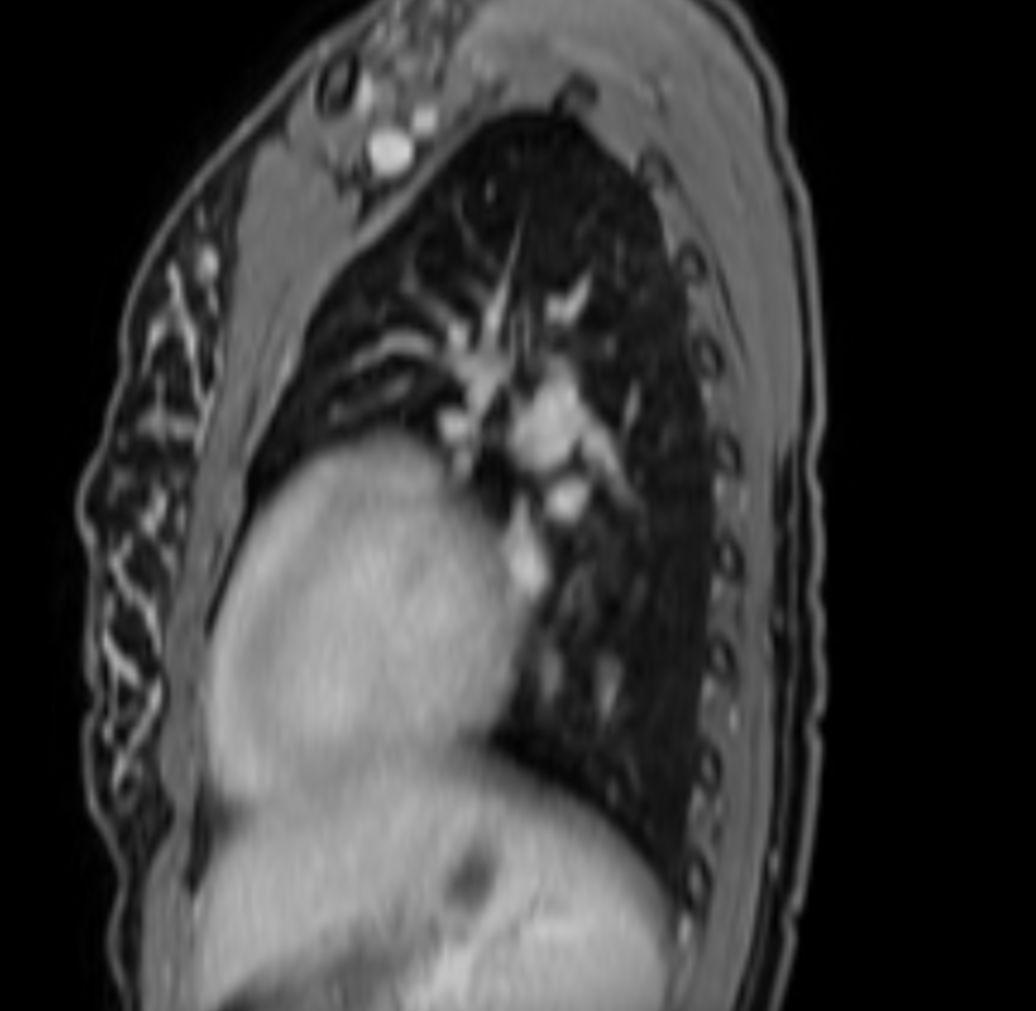

T2w SPIR - MultiVane XD